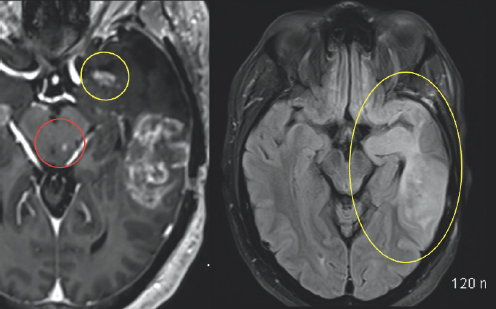

(Left) A variation of gray colored structures are surrounded by a black and white outline. On the top right of the image, there is a small white blob highlighted by a yellow circle. (Right) A variation of gray colored structures are surrounded by a large black and white outline. There is a small white blob in the center of the image highlighted by a red circle. There are two additional gray blobs with white coloration on them highlighted by two yellow arrows on the right side of the image.

FIGURE 2.5 Brain MRI after surgery. Imaging shows post-treatment and post-operative changes from resection of the left temporal tumor. There is interval decreased abnormal patchy enhancement within the medial left temporal lobe (yellow circle) and stable tiny enhancing lesion within the left aspect of the midbrain (red circle), which are also uncertain for residual tumor versus post-treatment changes.

White and light gray color variations are enclosed by a black and dark gray outline. There is significant white coloration on the right side of the image which is highlighted by a yellow oval.

FIGURE 2.6 Brain MRI after surgery. There is surrounding signal alteration on the MRI sequence image similar to the MRI before the surgery, which is nonspecific but likely represents swelling (yellow oval).

Initially, after the treatment, there was no obvious progression in his symptoms, but by mid-May of that same year, there was a dramatic decline in his condition (Fig. 2.4–2.7). Several concerning transient symptoms appeared, including confusion, lethargy, and significant memory loss, which impacted his compliance with his treatments and caused him to sometimes forget his regimen.